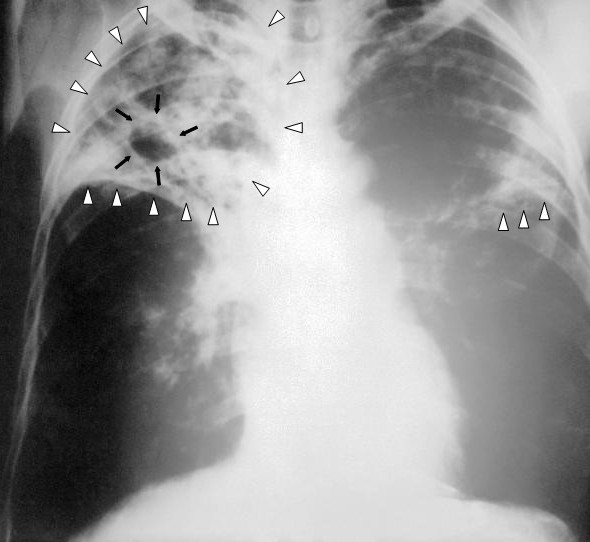

El diagnòstic es basa en la radiologia (habitualment radiografies toràciques), una prova de la tuberculina cutània i anàlisis de sang, així com una examinació al microscopi i un cultiu microbiològic dels fluids corporals. A la figura podeu veure una placa anteroposterior de raigs X d’un pacient diagnosticat amb avançat estat de tuberculosi en els dos pulmons. Aquesta radiografia del pit revela la presència d’una infiltració (triangles blancs) i una cavitat (fletxes negres) present en el costat dret. El diagnòstic és tuberculosi en un grau sever d’avanç.